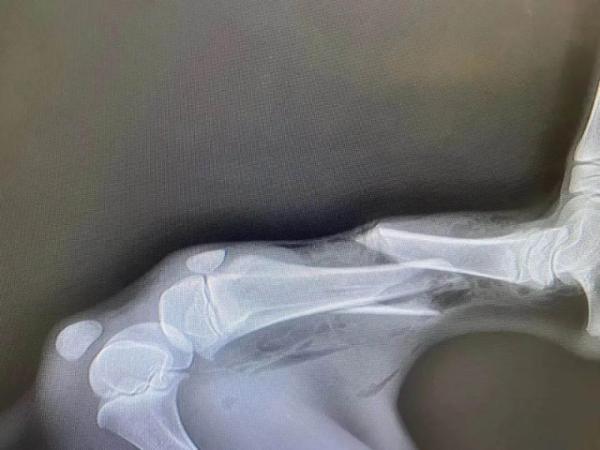

在小鹿的脊柱附近,有一处非常显眼的贯通伤口。“伤口直径不到1厘米,成弹丸状,从形状和大小看,小家伙很可能是遭遇了钢珠弹袭击!”“花花”表示。除此之外,这头小鹿的右后腿处开放性骨折。“花花”等人立即将受伤小鹿送往宠物医院进行救治。